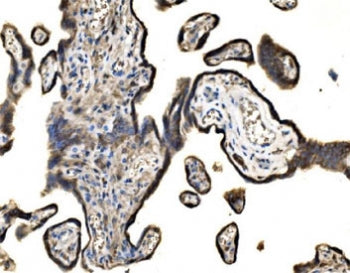

SND1 Antibody / Staphylococcal nuclease domain-containing protein 1 antibody / TDRD11

SND1 Antibody / Staphylococcal nuclease domain-containing protein 1 antibody / TDRD11